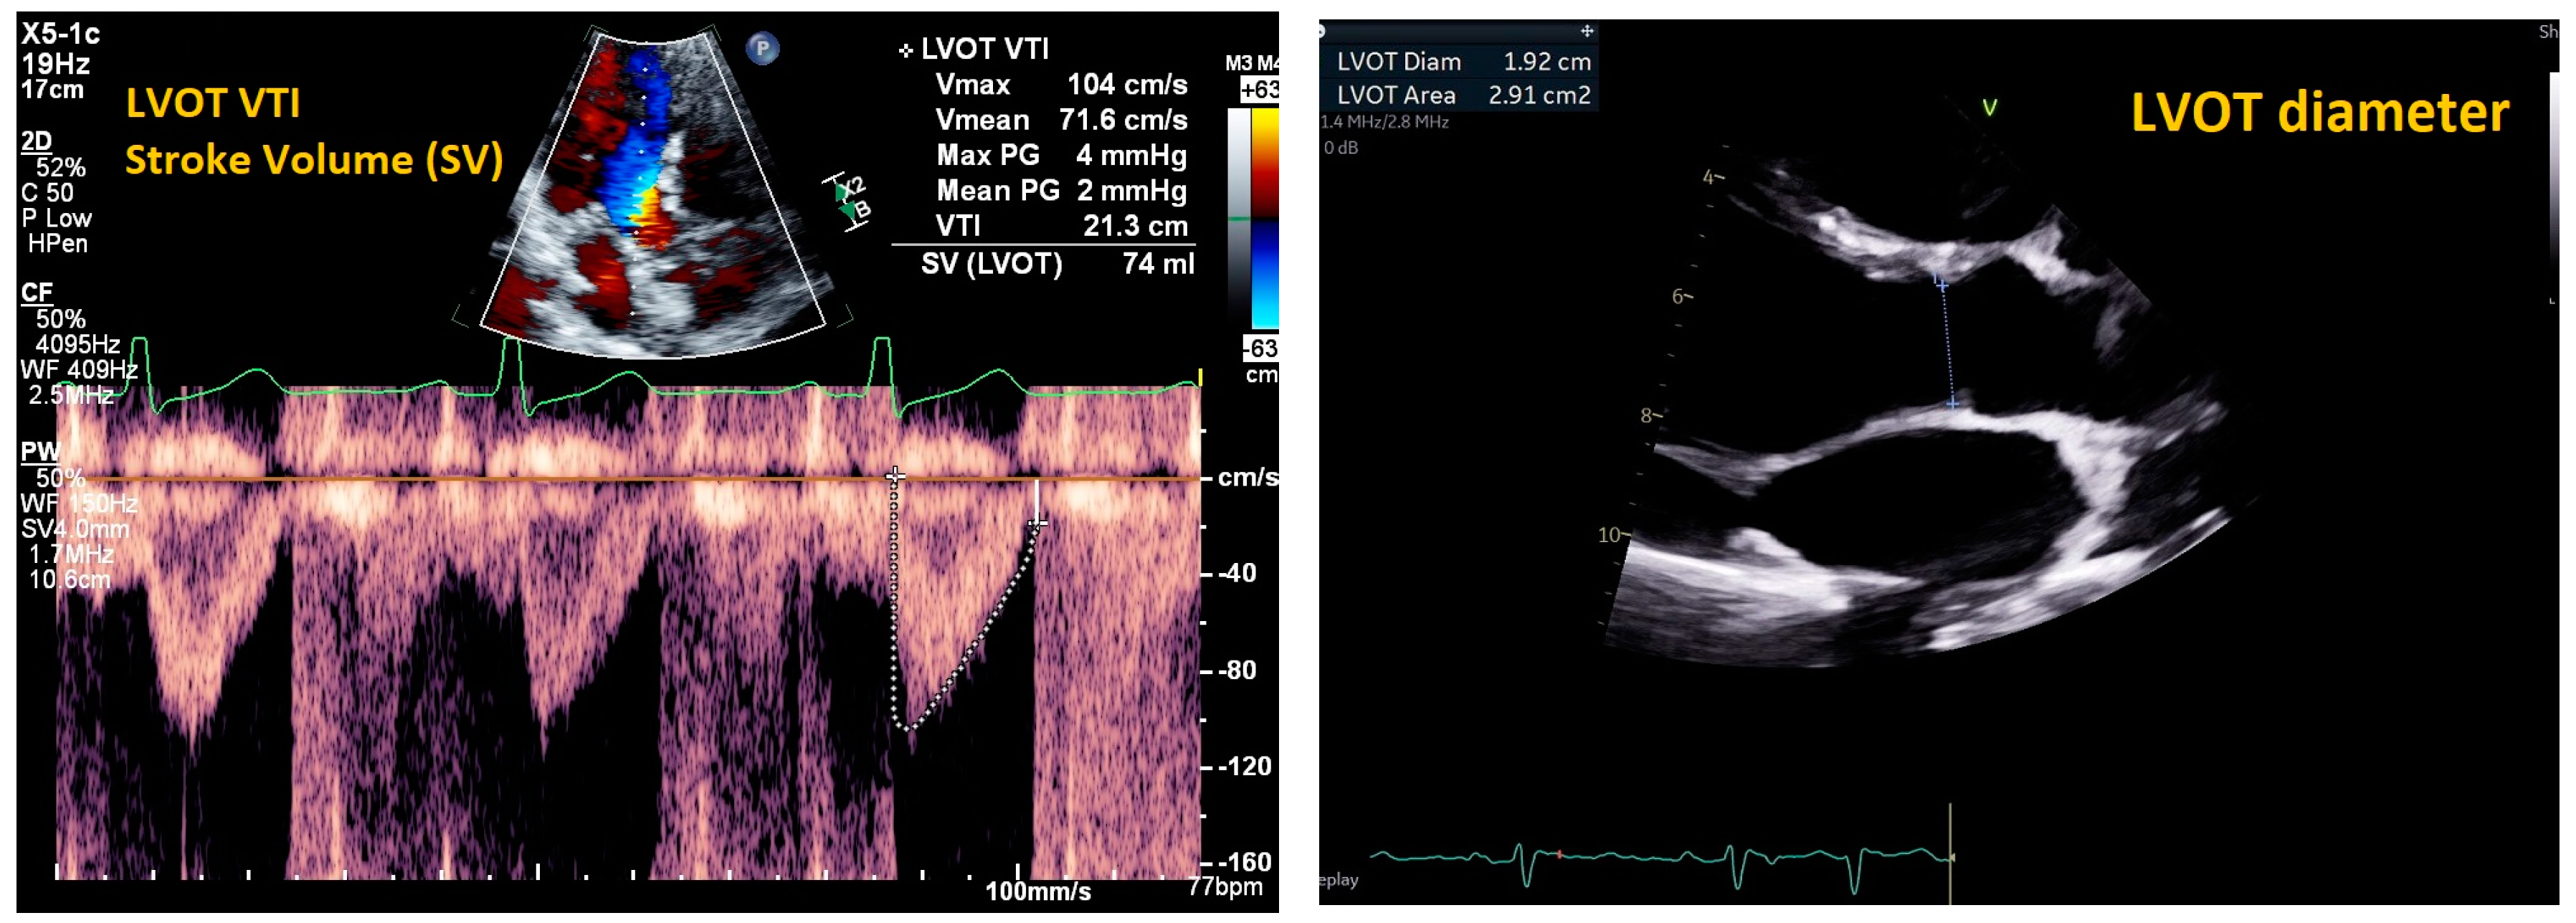

| Mitral E/e’ ratio estimated from the E wave velocity of the mitral inflow Doppler envelope and the tissue Doppler e’ wave velocity at the mitral annulus (septal and/or lateral) | E/e’ ≤ 14 |

|

| |